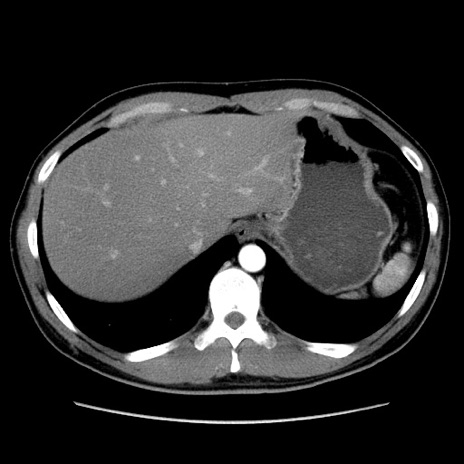

症例36(横断像)

【症例】20歳代 男性

【主訴】心窩部痛

【現病歴】今朝より上腹部痛あり。一旦軽快していたが再度出現したため救急要請。昨日夕に白身の魚を含む刺身を食べた。

【身体所見】BP 136/89mmHg、HR 74/min、BT 37.0℃、腹部:膨満、軟、心窩部に圧痛あり。反跳痛なし、筋性防御なし、腸雑音やや亢進あり。

【データ】WBC 17700、CRP 0.48